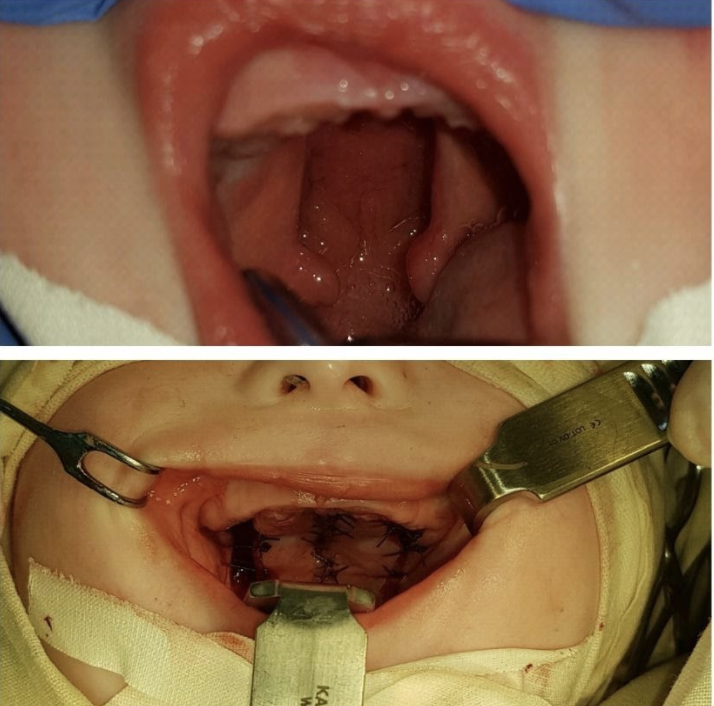

Приклади: наскрізне (повне) правобічне незрощення верхньої губи, носа, альвеолярного відростка, твердого і м’якого піднебіння

Двобічне незрощення, - праворуч наскрізне, ліворуч неповне незрощення верхньої губи і альвеолярного відростку та повне незрощення твердого і м'якого піднебіння.

Повне незрощення твердого і м’якого піднебіння; Неповне незрощення верхньої губи

Приклад одномоментної операції SRFM та ураностафілопластики

Дитина з ковтальними та дихальними розладами до операції

під час операції

після операції